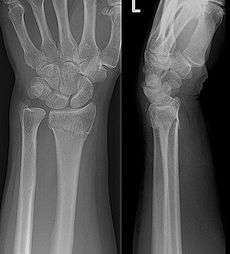

An X-ray image of a fractured radius showing the characteristic Colles' fracture with displacement and angulation of the distal end of the radius | |

A Colles' fracture is a fracture of the distal radius in the forearm with dorsal (posterior) and radial displacement of the wrist and hand.[1] The fracture is sometimes referred to as a "dinner fork" or "bayonet" deformity due to the shape of the resultant forearm. Colles' fractures are often seen in people with osteoporosis.

The fracture is most commonly caused by people falling onto a hard surface and breaking their fall with outstretched arms - falling with wrists flexed would lead to a Smith's fracture. It can also be caused by overuse. Originally it was described in elderly and/or post-menopausal women. It usually occurs about three to five centimetres proximal to the radio-carpal joint with posterior and lateral displacement of the distal fragment resulting in the characteristic "dinner fork" or "bayonet" like deformity. Colles' fracture is a common fracture in people with osteoporosis, second only to vertebral fractures.